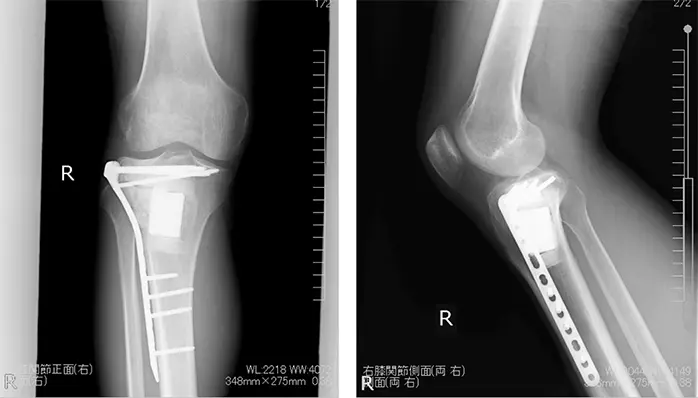

拡大掻爬術+フェノール処置+人工骨移植+プレート固定施行.生検時の皮切を利用し,前外側皮切で展開.脛骨外側を大きく開窓した後に周囲骨髄が出るまで掻爬を施行 (Figure 4).次にエアトームを用いて拡大掻爬後に熱焼却・フェノール処置を施行(Figure 5, 6).イメージ下に十分掻爬ができたことを確認後に,気孔率の高いOSferion®顆粒を軟骨下骨に充填後,下支えをするようにOSferion®ブロックを留置.その上で同OSferion®ブロックを支えるように気孔率60のOSferion®ブロックを充填(Figure 7).次にシンセス社製外側用Locking Compression Plate (LCP)を設置(Figure 8).近位軟骨下骨にrafting screwとしてlocking screwを4本挿入,遠位にもlocking screwを4本挿入固定.骨内にアミカシン5A注入,ドレーンを留置し追層縫合,閉創し,手術終了となった.術直後に正面像および側面像を撮影し,明らかな異常認められないことを確認した(Figure 9).